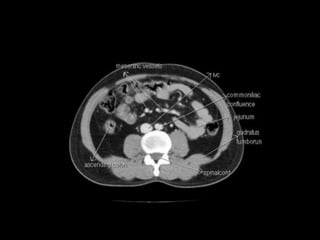

Cross section anatomy of abdominal ct scan

Cross section anatomyof abdominal ct scan